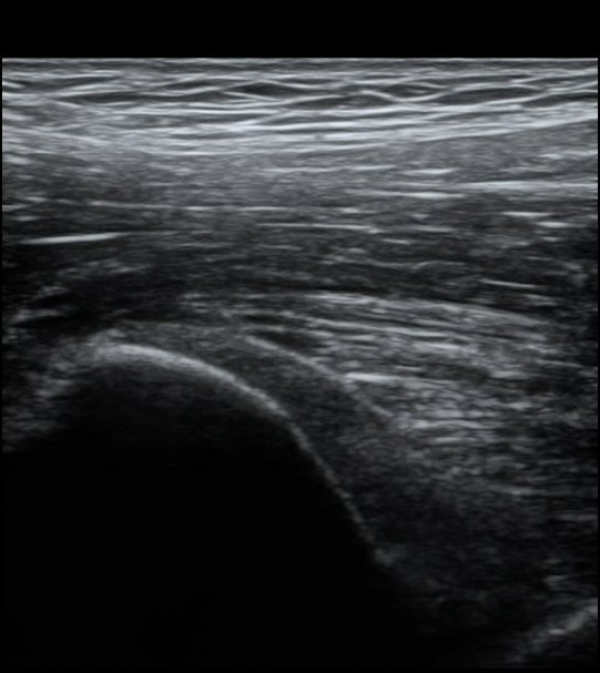

ÀÌ º´Àû º¯È­´Â Á¤»óÃø(»çÁø 6, 7)°ú ºñ±³ÇÏ¸é ¶Ñ·ÈÇÏ´Ù.)

´ëÅðÁ÷±Ù ÈûÁ٠Ⱦ´Ü¸é °Ë»ç¿¡¼­µµ ÈûÁÙÀÇ Àú¿¡ÄÚ º¯È­¸¦ º¸À̰í(»çÁø 4, 5) ÀÌ º´Àû º¯È­µµ

°ÇÃø(»çÁø 6, 7)°ú ºñ±³ÇÏ¸é ½±°Ô ÆÇ´ÜµÈ´Ù.